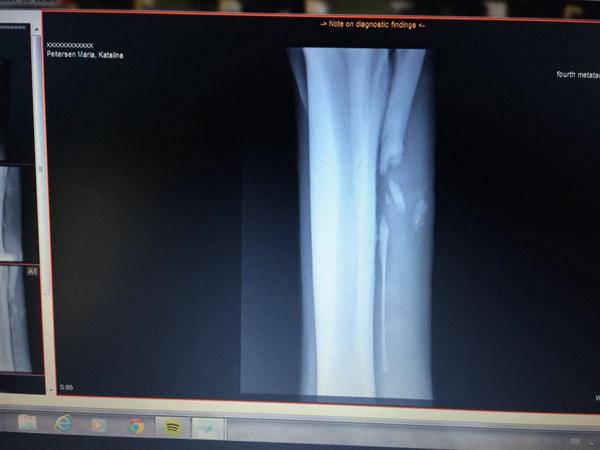

Min hest gennemgik en operation for et brækket bagben, d.22/10 og har i alt stået stille 4 måneder.

• #2   7. jan 2015 Min hest havde samme skade som din, brækket griffelben. Skaden skete i slut feb. I juni blev hesten opereret ( de var længe i tvivl om det selv ville gro sammen, så derfor den lange tid). Hesten stod på sygefold i 8 uger. Derefter 4 uger på alm fold med rolig ven. I august blev hesten godkendt til genoptræning. I start dec var genoptræning færdig. I slut dec begyndte jeg på undervisning igen, dog med forbehold. Vi rider næsten helt normalt nu, men mangler selvfølgelig stadig muskler, kondition og at få styrket sener mm.